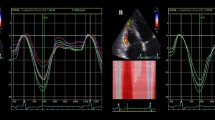

The average maximum cross-correlation between the volume obtained by 3D-ultrasound and the circumferential strain obtained by tagged MRI was r 2 = 0.65 ± 0.19. The mean intermodality delay at maximum cross-correlation was −1.9 ± 12.4 time-lags, which is significant (95% confidence interval: −3.2 to −0.6 time-lags) and corresponds to an average time-delay of −16.9 ± 112.8 ms. The negative sign indicates that the strain curve was delayed with respect to the volume curve. The accompanying average regression coefficient was 43.0 ± 5.6%cm−1 (mean ± SE), and the constant was −87.2 ± 10.9% (mean ± SE). An example of the volume and strain curves and cross-correlations for one patient can be seen in Fig. 1.

Strain, volume and cross-correlation curves of all segments in one patient. From top to bottom: base, mid, apex. From left to right: inferoseptal, anteroseptal, anterior, anterolateral, inferolateral and inferior segments (apex: septal, anterior, lateral, inferior). In the cross-correlation curves, a positive peak cross-correlation value depicts that the strain curve reached its peak before the volume curve. Cross-correlation curves marked with * indicate a segment with DCE

DCE